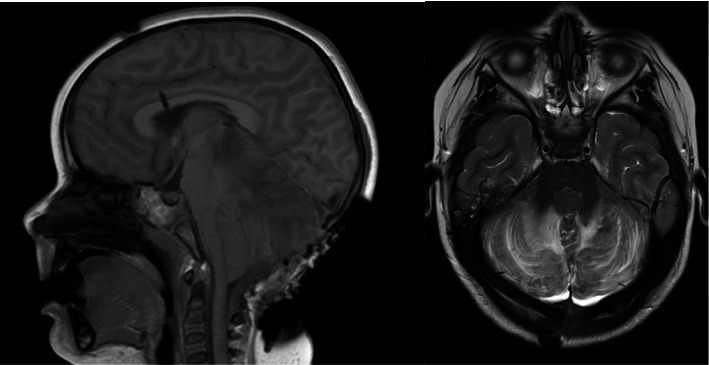

美沙酮是一种用于治疗疼痛和阿片类药物依赖的合成阿片类药物。尽管它的好处,意外摄入美沙酮在儿科患者可导致显著的发病率和死亡率。儿童摄入美沙酮引起的急性毒性包括脑白质病和小脑炎。对儿童美沙酮过量后的治疗和影响临床结果的因素的研究有限。我们报告一个3岁的儿童严重脑损伤和死亡后意外摄入美沙酮。我们的病例是独特的,因为我们能够获得摄取后的血清美沙酮水平,这是用来指导干预和治疗。通过这个案例,我们的目的是促进对美沙酮毒性的日益了解,同时也倡导实施保护我们儿科人口的政策。

Methadone is a synthetic opioid used to treat pain and opioid dependence. Despite its benefits, accidental ingestion of methadone in pediatric patients can lead to significant morbidity and mortality. Documented findings of acute toxicity secondary to methadone ingestion in children include leukoencephalopathy and cerebellitis. There is limited research into treatment and factors influencing clinical outcomes following methadone overdose in children. We report a 3-year-old child with severe brain injury and death following accidental ingestion of methadone. Our case is unique in that we were able to acquire a serum methadone level following ingestion, which was used to guide intervention and treatments. Using this case, we aim to contribute to the growing understanding of methadone toxicity while also advocating for the implementation of policies that protect our pediatric population.